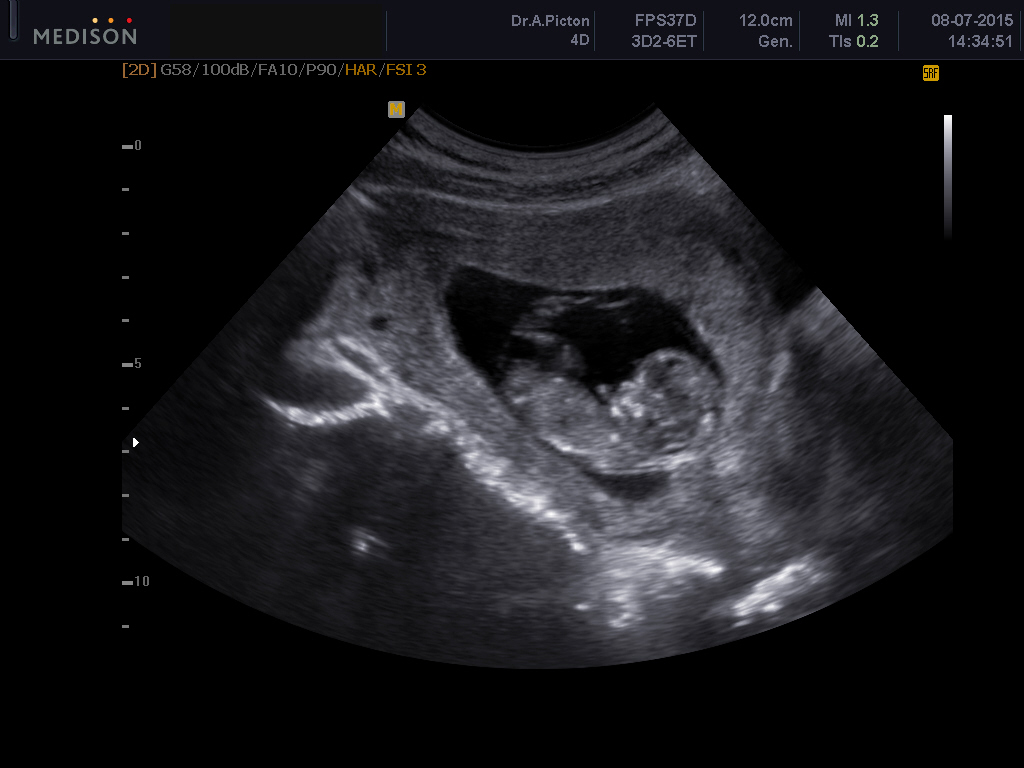

I had my first ultrasound on July 7th. It was great. My little peanut is such a wiggle worm. He/she would not sit still long enough to get good pictures. But they still managed. I was 13 weeks and 3 days, but now measuring at 14 weeks with a heartbeat of 161. Still don't know the gender, I can't wait to find out though. For some reason it won't let me post a picture.